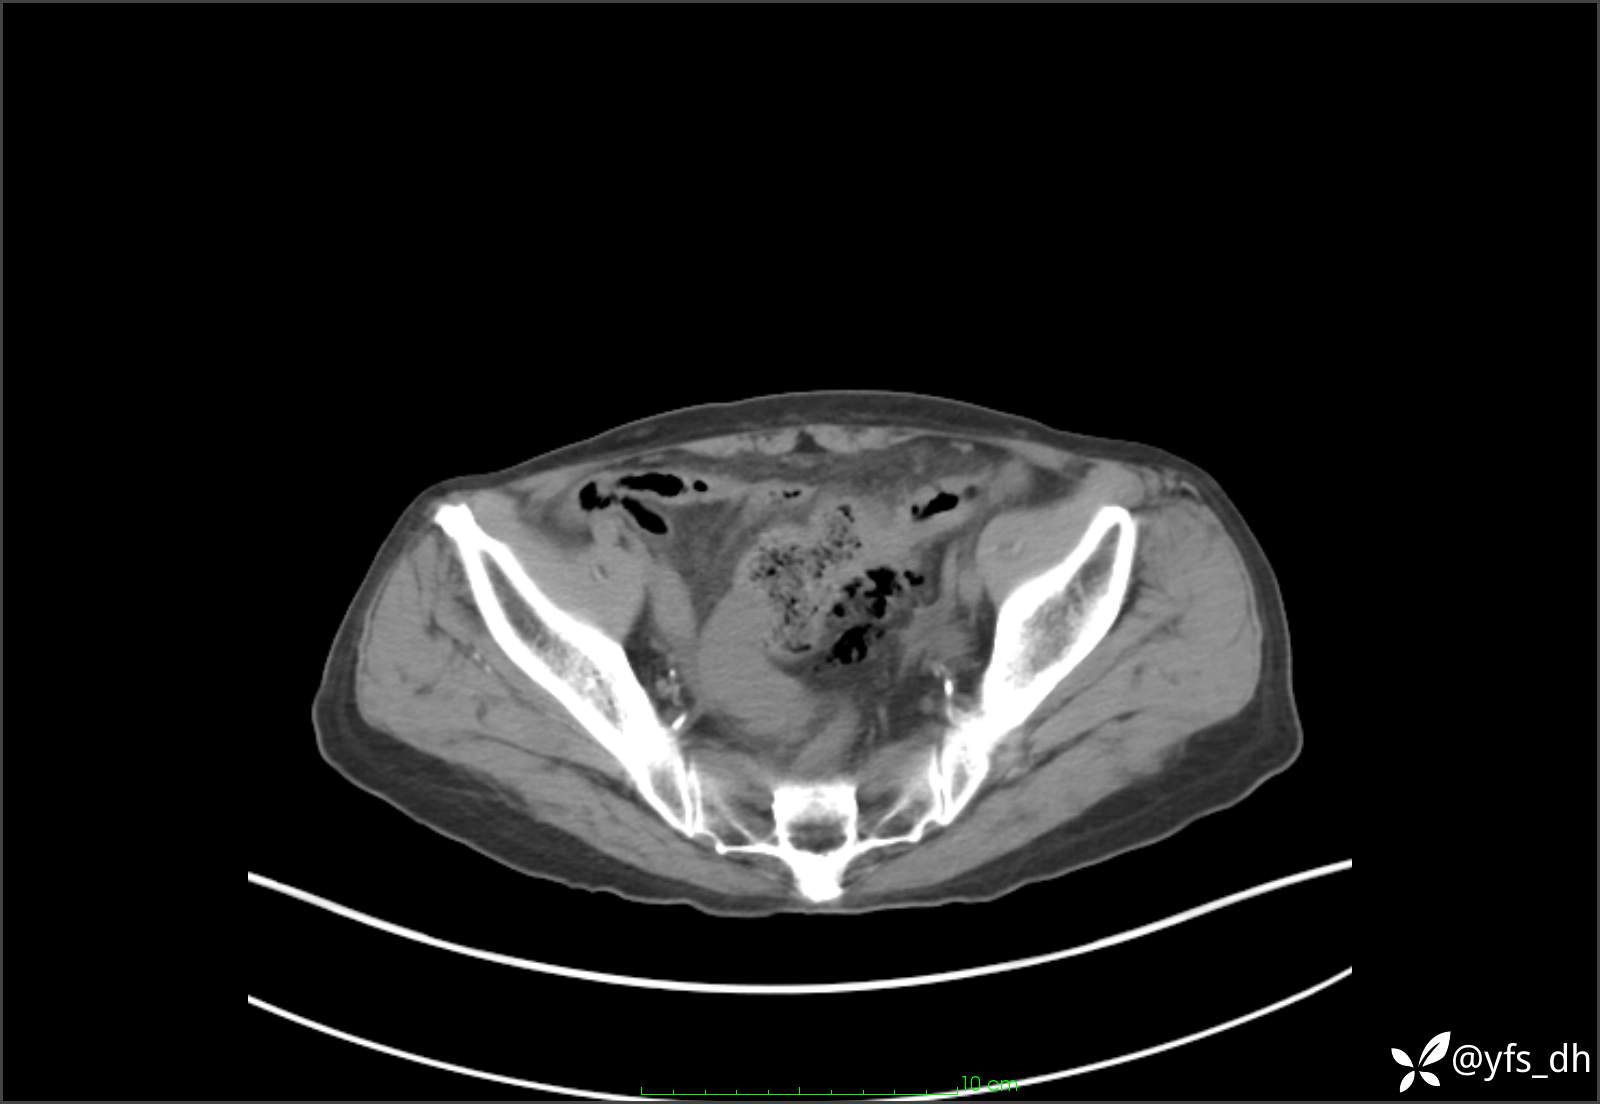

1.简要病史:患者4天前突发上腹部疼痛不适,但可以忍受。3小时前饭后突然加重,不能忍受后就诊。

2.简要手术记录:术中见腹盆腔大量肠液及粪便,乙状结肠中下段见一约3cm的破口。